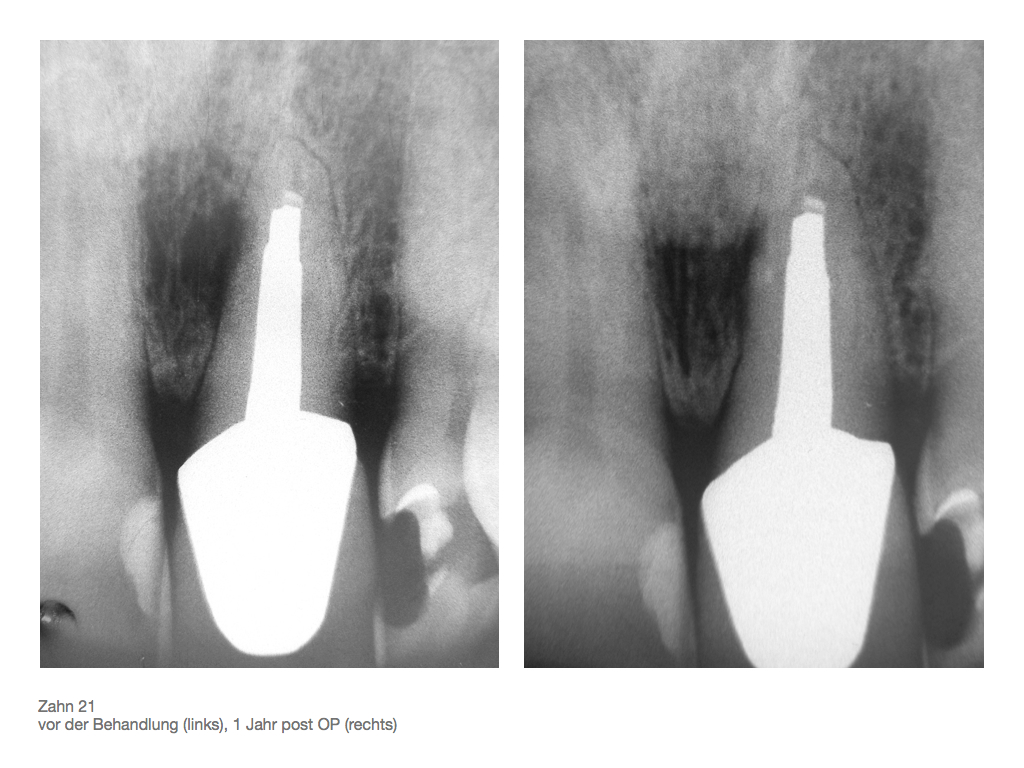

Rö – Bilder 21 – vor und nach OP Veröffentlicht 17. März 2009 am 1024 × 768 in Seitenkanal Rö – Bilder 21 – vor und nach OP